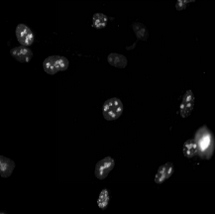

1、細(xì)胞生物學(xué):用于觀察細(xì)胞結(jié)構(gòu)、動態(tài)和相互作用。

3、遺傳學(xué):用于基因表達研究和蛋白質(zhì)定位。

03場景圖/實拍效果圖